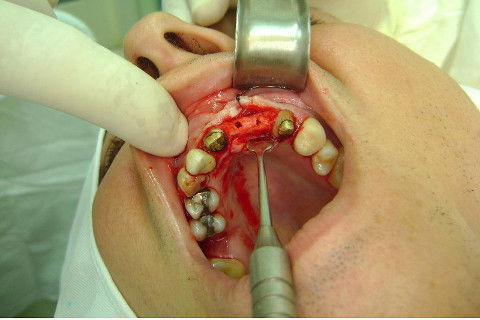

Cirurgia realizada hoje de manhã...No planejamento percebi medindo espessura do rebordo com especímetro que as medidas não estavam muito boas, ou o ideal, em torno de 4,5 a 5 mm ate´o terço médio do rebordo e melhorava no final, com 6 a 7 mm. Optei então por uma pequena expansão usando os expansores rosqueáveis. Aconteceu uma pequena fenestração na hora da fixação dos implantes, especialmente na região do 22 que fraturou o início da tábua óssea, mas não me preocupei porque não foi mais do que 2 mm de fratura em direção apical, o implante ficou infraósseo e com boa estabilidade (60 N no 21 e 40 N no 22). Esta fratura tb não deixou osso completamente solto, foi do tipo galho verde, deixei em posição e suturei normalmente. Só não fiz e nem estava planejado carga imediata mesmo, mais pelo motivo da oclusão inadequada do caso.

Fotos do caso